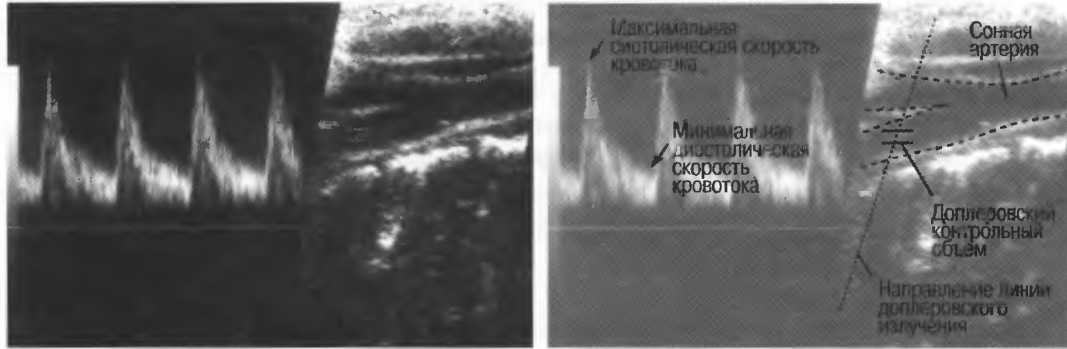

4. Режим дуплексного доплеровского сканирования. Кровеносный сосуд изображается в В-режиме, скорость кровотока определяется доплерографически. Такое сочетание В-режима и доплерографии позволяет более точно получить информацию с данного конкретного сосуда (рис. 2в,г).

Рис.2в. Дуплексное доплеровское сканирование внутренней сонной артерии. В левой половине представлена кривая скоростей кровотока, демонстрирующая пульсирующий поток по направлению к датчику. Если бы поток был направлен от датчика, то спектр скоростей кровотока был бы направлен вниз от изолинии. Кривая скоростей носит волновой характер в соответствии с сердечным циклом. В правой половине развертки представлено изображение в В-режиме, которое показывает, откуда был снят спектр скоростей кровотока.

Рис.2г. Результаты исследования могут быть искажены, если угол сканирования выбран неправильно. Это та же общая сонная артерия, представленная на рис. 2в, однако угол сканирования составляет около 90°. В результате поток выглядит турбулентным, хотя на самом деле он совершенно нормален. В данном случае неправильно выбран угол сканирования, а с потоком все в порядке.